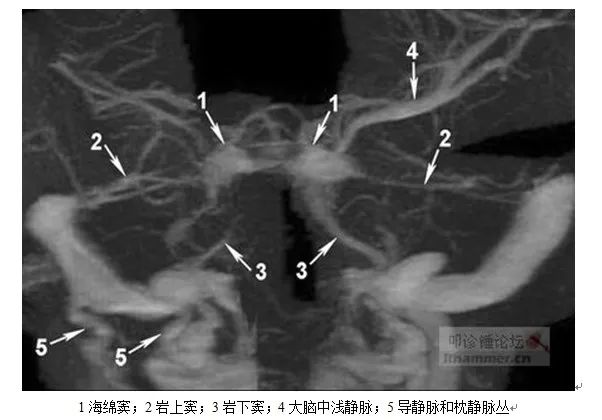

1.海绵窦、海绵间窦:蝶鞍两侧两侧硬脑膜内,多发结缔组织形成多个小腔,呈海绵状。左右海绵窦之间,鞍膈前后附着缘,前面为海绵间前窦,后面为海绵间后窦,连同左右海绵窦,环绕垂体形成环窦。此外,在蝶鞍底部还有海绵间下窦,位于垂体下面多呈裂隙状,回流垂体静脉(海绵间下窦大小对经鼻垂体腔镜术时非常重要)。

向前借眼上静脉、内眦静脉回流至面静脉,借眼下静脉回流至翼静脉丛;向上借大脑中浅静脉,经其上吻合静脉(Trolard静脉)回流至上矢状窦,经其下吻合静脉(Labbe静脉)回流至横窦;相后借岩上窦回流至横窦,借岩下窦回流至颈内静脉或乙状窦,借基底静脉丛与椎内静脉丛相连。

2.岩上窦:位于小脑幕附着于颞骨岩部上缘的沟内,前通海绵窦,后通横窦。收集小脑静脉、大脑下静脉和鼓室静脉,与岩下窦和基底静脉丛交通。

3.岩下窦:位于颞骨岩部后面下缘的岩枕裂内,前通海绵窦后下,后通颈静脉上球或乙状窦,收集蜗小管和前庭小管的迷路静脉和来自脑桥、延髓和小脑下面的属支。